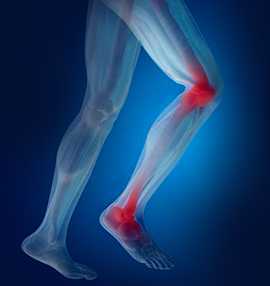

В последние годы специалисты всего мира отмечают рост дегенеративно-дистрофических процессов в голеностопе, постепенно приводящих к инвалидности. Артроз голеностопного сустава часто развивается в результате серьезных травм или постоянного микротравмирования у спортсменов, профессиональных танцовщиков, цирковых артистов. Как своевременно заметить признаки этого заболевания и остановить его прогрессирование, а также, как лечат его в московской клинике «Парамита», вы узнаете из этой статьи.

Артроз голеностопного сустава - это дегенеративно-дистрофическое заболевание, начинающееся с истончения и разрушения суставного хряща, снижения его амортизационных свойств, с последующим включение в патологический процесс всех остальных суставных тканей. Болезнь постепенно приводит к полному износу сустава и инвалидности. Код артроза голеностопного сустава мкб 10 - М19.

Заболевание встречается реже, чем аналогичное поражение колена и обычно бывает следствием серьезных травм или длительного травмирования в результате какой-либо деятельности.

Симптомы артроза голеностопного сустава

Артроз голеностопа протекает медленно и вначале незаметно. Но постепенно появляются и нарастают симптомы, сигнализирующие о каких-то нарушениях в нижней конечности.

Первые признаки

Самый первый симптом артроза голеностопа - это боль при высоких нагрузках, например, при длительном хождении, танцах, игре в футбол или волейбол и т.д. Эта боль быстро проходит, поэтому человек не сразу обращает на нее внимание, списывая на мышечную усталость. Боли могут быть, как симметричными, в обоих суставах (при высоких нагрузках и микротравмах), так и односторонними (после перенесенной крупной травмы).

Потом появляется ощущение скованности по утрам или после длительного пребывания в неподвижном состоянии. Голеностоп на некоторое время становятся тугоподвижными, что затрудняет движение. На начальных стадиях это длится несколько минут и проходит после медленного расхаживания. Этот симптом уже должен насторожить и стать поводом для обращения к врачу.

Явные симптомы

Постепенно боли после нагрузок усиливаются, продолжаются все дольше. Нога может болеть весь день. Присоединяются ночные боли, обычно она появляются во второй половине ночи и иногда сопровождаются болезненными мышечными судорогами. Периоды скованности после неподвижности также удлиняются.

Из-за выраженных болевых ощущений человек начинает хромать по время ходьбы, пытается уменьшить боль в стопе, вытягивая или поджимая ее. Иногда голеностоп отекает, кожа над ним краснеет, боли усиливаются. Это признак синовита - воспаления внутренней синовиальной оболочки. Воспаление носит неинфекционный характер, развивается от механического раздражения и проходит самостоятельно без лечение. Но в то же время обострение синовита активизирует прогрессирование суставного дегенеративно-дистрофического процесса.

Опасные симптомы

Постоянные ноющие боли, усиливающиеся при физических нагрузках, нестабильность, разболтанность сустава, склонность к подвывихам, вывихам и травмам связок - опасные симптомы, требующие обращения к врачу. Голеностоп изменяется внешне: он приобретает другую форму из-за разросшихся остеофитов. Артроз щиколотки (лодыжки) приводит к ее утолщению. Движения в стопе вначале слегка ограничиваются, а потом голеностоп становится неподвижным или наоборот, разболтанным, нестабильным. Но и на этой стадии пациенту можно помочь, нужно просто обратиться в клинику. Появляются симптомы артроза стопы: боли в ступне, нарушение ее сгибания и амортизации. Развитие артроза большого пальца стопы сопровождается болями и деформацией стопы в виде выпирания загибания большого пальца кнаружи.